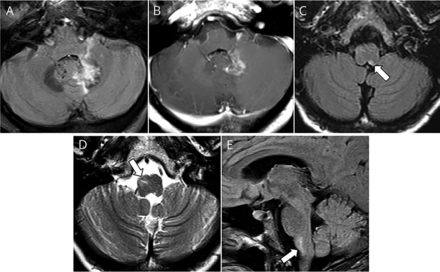

图1

大脑核磁共振(上面一行)和发病后9个月(底下一行)

轴向图像显示T2 hyperintensity左齿状(A),以增强postgadolinium (B),和区域postrema T2 hyperintensity (C),重复MRI显示正确的下橄榄核T2 hyperintensity /肥大轴向(D)和矢状图像(E)。